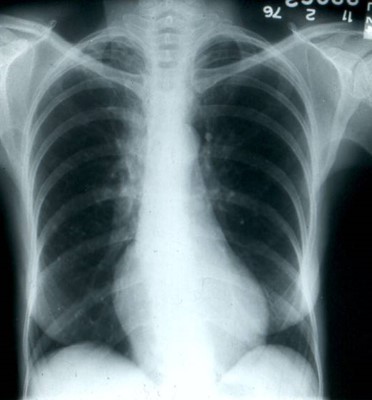

Her chest x-ray and a photo of her arm lesion are shown below.

The source of the dissemination in the presented case was her lungs. Although

her chest x-ray was free of infiltrates, a ventilation profusion scan showed multiple

wedge-shaped areas of non-profusion, findings characteristic of infarction (see left

lower photo, above).